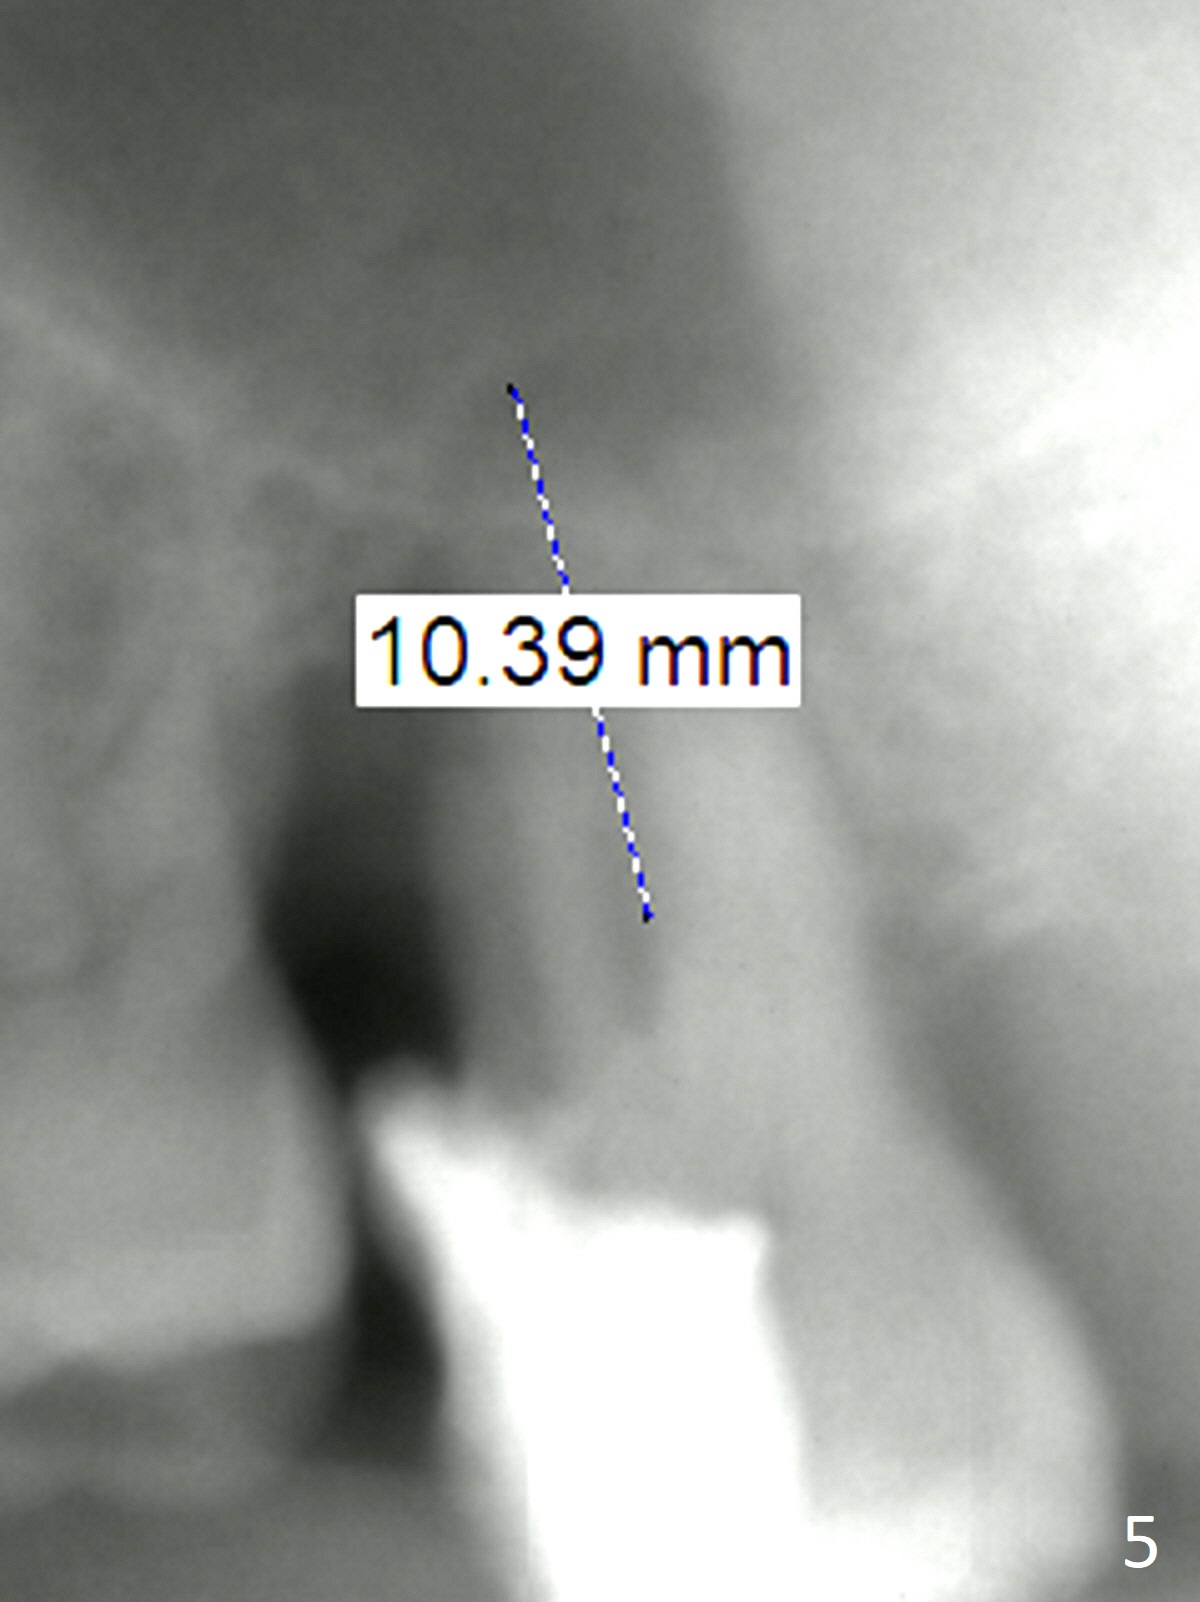

Bone loss seems to be the most severe around the mesiobuccal root (Fig.2 *), from which the osteotomy should stay away (Fig.3).  It may be the safest to place an implant in the palatal socket, leaned as buccally as possible so that the coronal end of the implant will be in the center of the extraction socket.  Re-measure the palatal socket length from PA and Pan: 8.5 and 10 mm, respectively.  The implant length should be around 10 mm.  Place bone graft before the final tap and take X-ray.